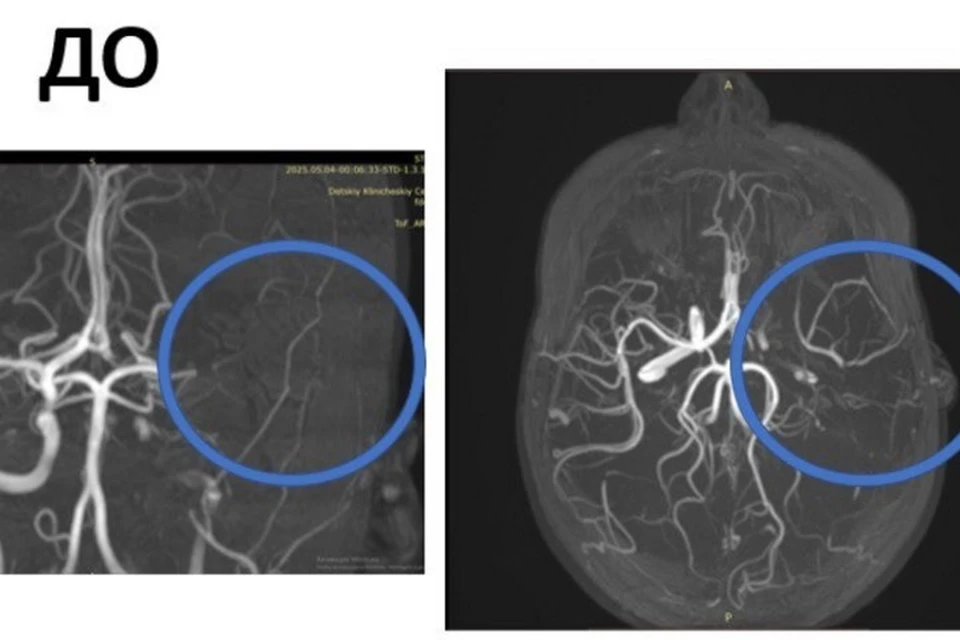

Специалисты сделали томографию, которая исключила кровоизлияние. МРТ показало, что у пациентки инсульт левого полушария мозга. Без операции она могла стать инвалидом или умереть. Сейчас состояние девочки стабильное, она восстанавливается в отделении неврологии.